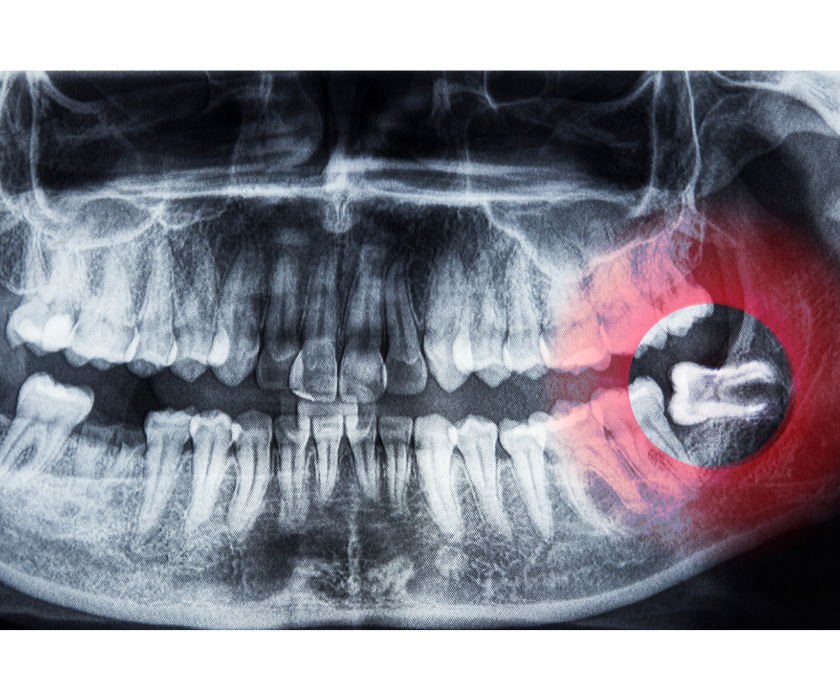

Răng khôn mọc lệch, mọc ngầm:

Răng khôn không có đủ khoảng trống để mọc thẳng thường sẽ mọc lệch sang răng số 7 (răng hàm kế cận), đâm vào mô mềm hoặc thậm chí đâm ngang vào xương hàm. Điều này không chỉ gây đau nhức dai dẳng mà còn có thể làm tổn thương chân răng bên cạnh, gây tiêu xương và sâu răng lây lan.

Răng khôn mọc lệch, ngầm hay không có răng cắn đối diện thì cần nhổ bỏ